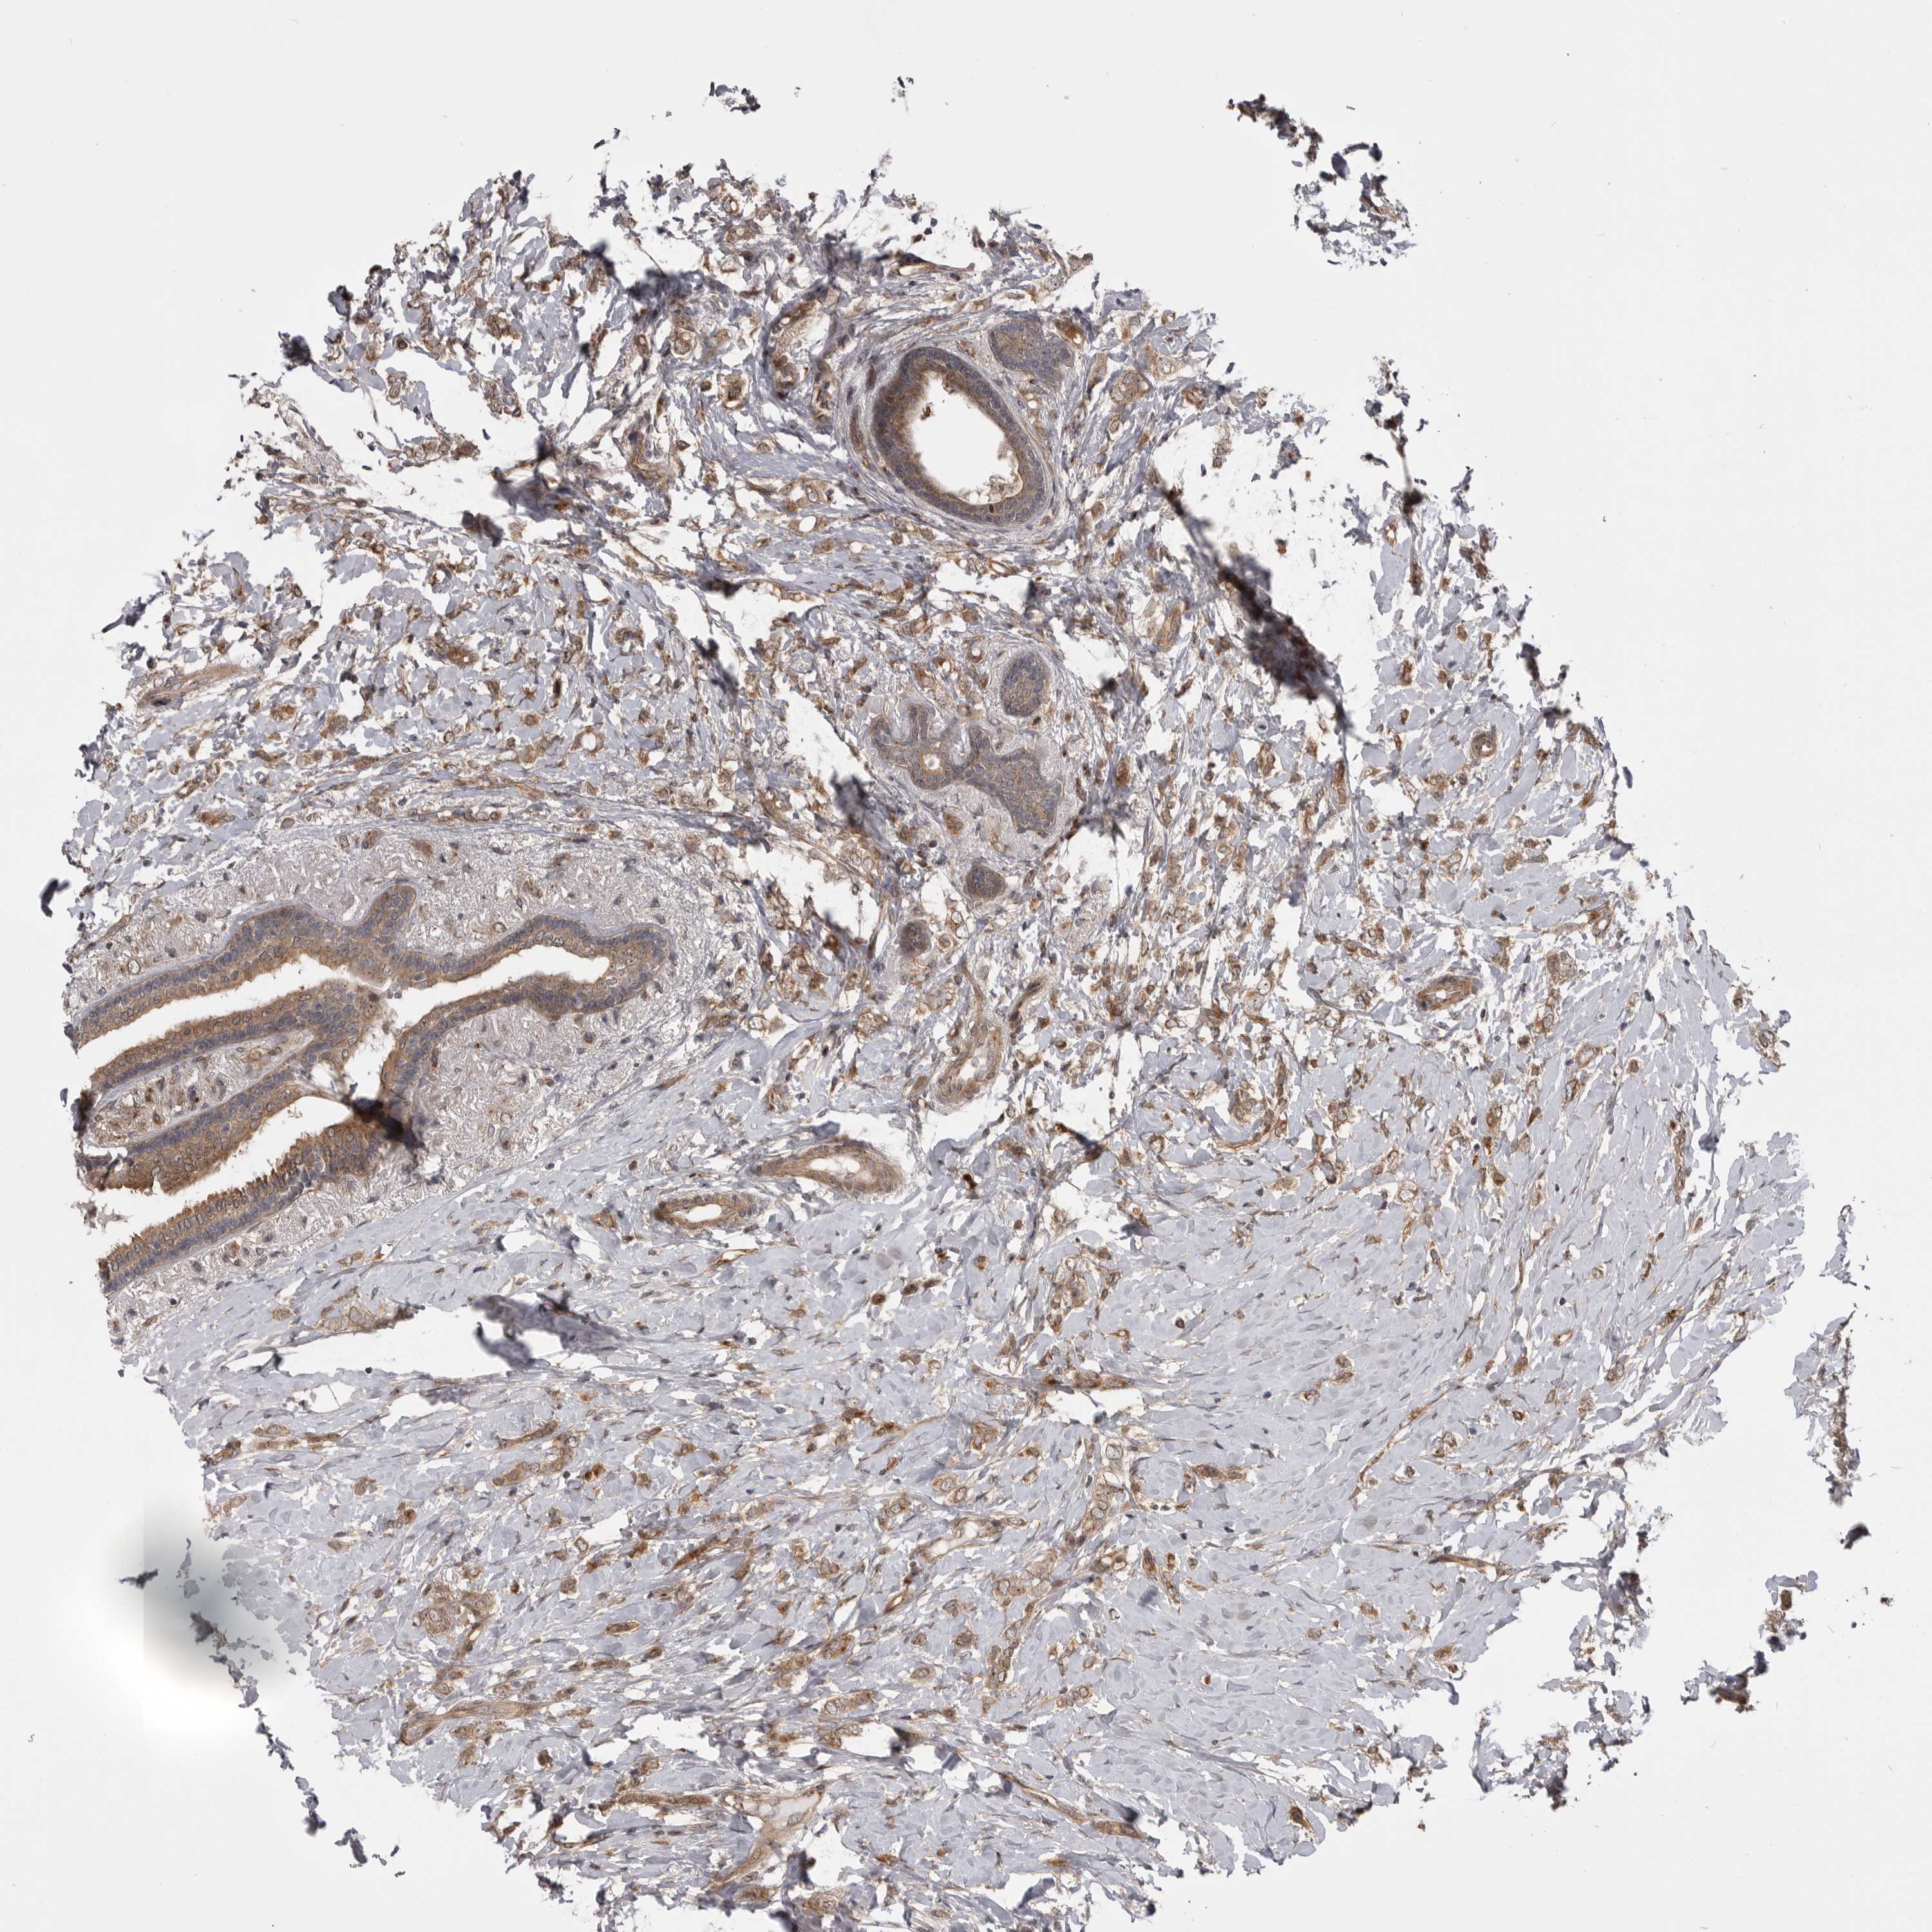

CANCER BREAST CANCER Show tissue menu

BRCA TCGA BRCA VALIDATION PROTEIN EXPRESSION

ANTIBODIES

AND

VALIDATION